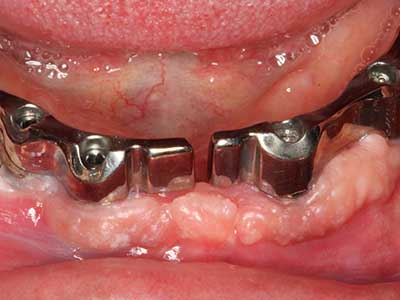

Fig. 13: En este paciente de 52 años con una anchura del hueso residual del maxilar inferior de 4 mm, hay que asegurarse de que exista refrigeración por agua adecuada durante la partición del hueso.

Fig. 14: Incorporación de cuatro implantes RSX cónicos (Bego Implant Systems, Bremen).

Fig. 15: El control radiológico realizado al cabo de un año muestra una estabilidad del nivel óseo.

Fig. 16: También condiciones intraorales estables con incorporación de los implantes en la encía queratinizada.

Fig. 17: Tomografía computarizada de un osteoma de crecimiento progresivo ...